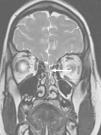

A los 30 meses, ingresa nuevamente por meningitis por H. influenzae no serotipificable. Los padres explican clínica previa indicativa de otitis de oído derecho. Al tratarse de un segundo episodio de meningitis bacteriana, se realiza un estudio inmunológico completo que resulta normal, incluyendo serología a virus de la inmunodeficiencia humana (VIH), inmunoglobulinas séricas, estudio de vías clásica y alternativa del complemento, presencia de bazo en ecografía y ausencia de cuerpos de Howell-Jolly en sangre periférica. Ante la recurrencia de una meningitis por gérmenes característicos de la flora ótica-orofaríngea se decide descartar un defecto anatómico a este nivel. Así, se amplía el estudio de imagen con la realización de una TC de peñasco de alta resolución y resonancia magnética (RM) craneal, donde se aprecia una malformación del laberinto membranoso que afecta a la cóclea y el vestíbulo en el lado derecho (partición incompleta tipo ii o deformidad de Mondini), considerándose el origen de la meningitis recidivante por fístula al espacio subaracnoideo (fig. 1).

TC y RM de peñasco. a) Imagen axial de TC de alta resolución. b) Imagen axial CISS (three-dimensional constructive interference in steady state) de RM. Malformación del laberinto membranoso que afecta a la cóclea y el vestíbulo en el lado derecho (partición incompleta tipo ii o deformidad de Mondini) (flechas negras).